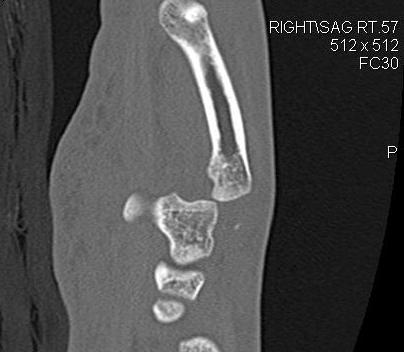

5. MCPJ Dislocation

Complex

- volar plate, lumbricals, flexor tendons interposed

- open reduction

Vumedi open reduction irreducible MCPJ dislocation